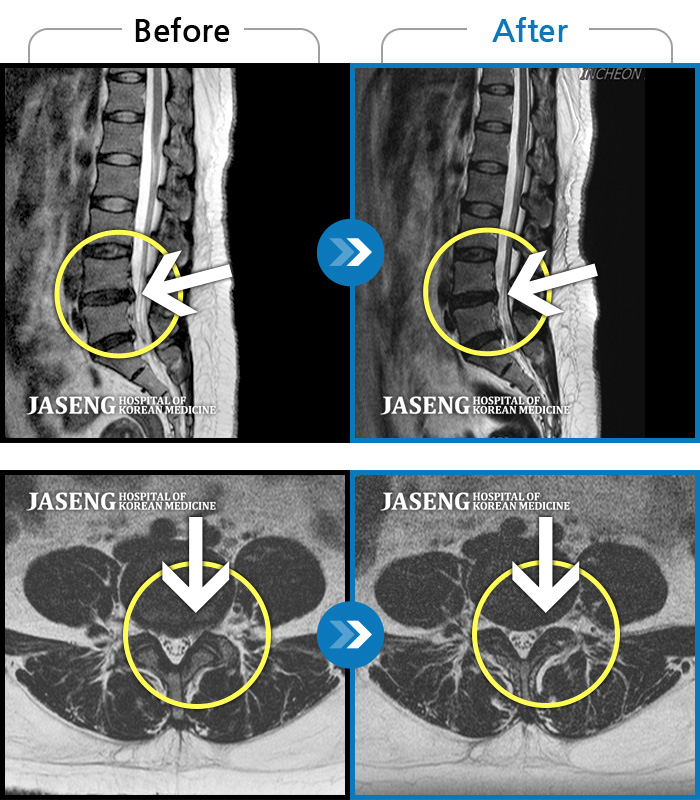

MRI 치료사례

극심한 통증으로 허리를 조금도 움직이기 힘들었고, 오른쪽 허벅지 전면부 찌릿한 통증